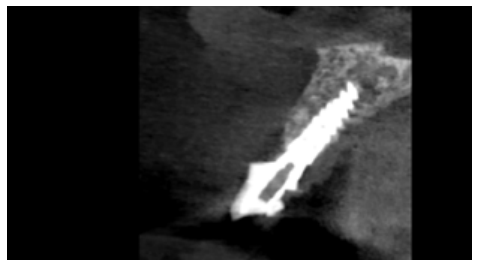

A radiological examination was carried out that included a periapical radiograph and a CBCT to appreciate the distribution of the ULCI fracture better (Figure 2).

The radiographic examination confirmed an oblique fracture that included the region of the middle third of the root and extended in a coronal-palatal direction towards the coronal region. Likewise, the presence of normal root canal treatment and the absence of a vestibular plate in the region of the two coronal thirds of the ULCI root was observed.